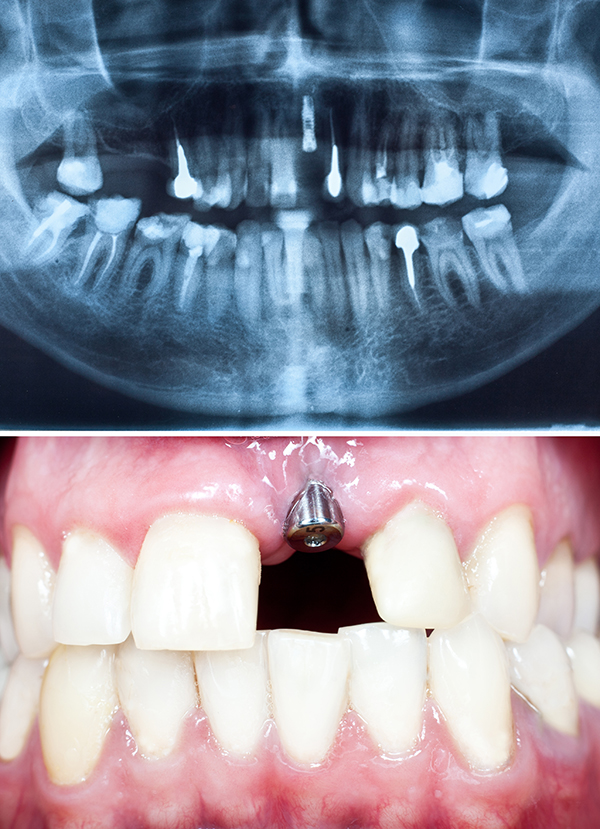

임플란트 치료 기간의 가장 중요한 포인트는 바로 잇몸뼈의 여부입니다. 만약 잇몸뼈가 충분하다면 일반적으로 3~4개월 정도면 충분할 수 있는데, 잇몸뼈가 부족하다면 뼈이식을 해야 하므로 기간이 더 길어질 수 있습니다. 잇몸뼈가 부족한 경우 뼈이식 수술을 통해 잇몸뼈를 보강해야 하며, 이는 임플란트 치료 기간을 6개월 이상으로 연장할 수 있습니다. 따라서 초기 상담 시 잇몸뼈 상태를 정확히 진단받는 것이 중요합니다.

일반적으로 우리나라에서 시술하는 임플란트 가격은 평균 80만 원 ~ 200만 원까지 매우 다양합니다. 이렇게 회사마다 가격 차이가 많은 이유는 픽스처 재료값의 차이 때문입니다. 픽스처란 자연치아의 뿌리 역할을 하는 구조체라고 생각하시면 됩니다. 픽스처의 재질과 제조 공정에 따라 가격 차이가 발생하며, 이는 임플란트의 내구성과도 직결됩니다.